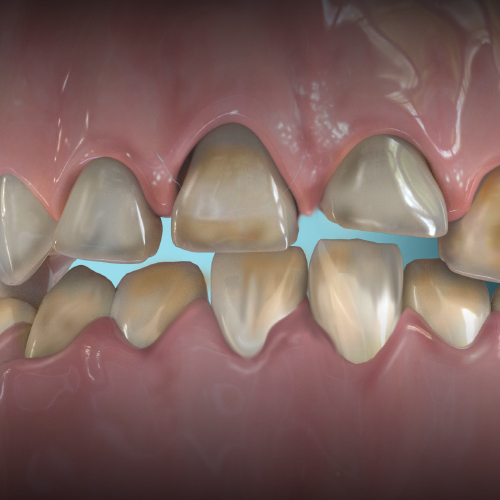

Prevention of Tooth Wear in Patients With Bruxism

Loray Spencer, DDS

Tuesday, July 11, 2023

An important aspect in preventing tooth wear is identifying and managing its potential causes, such as bruxism and malocclusion. This Compendium eBook offers a continuing education (CE) article on the diagnosis and management of bruxism, as well as orthodontic treatment for the correction o...